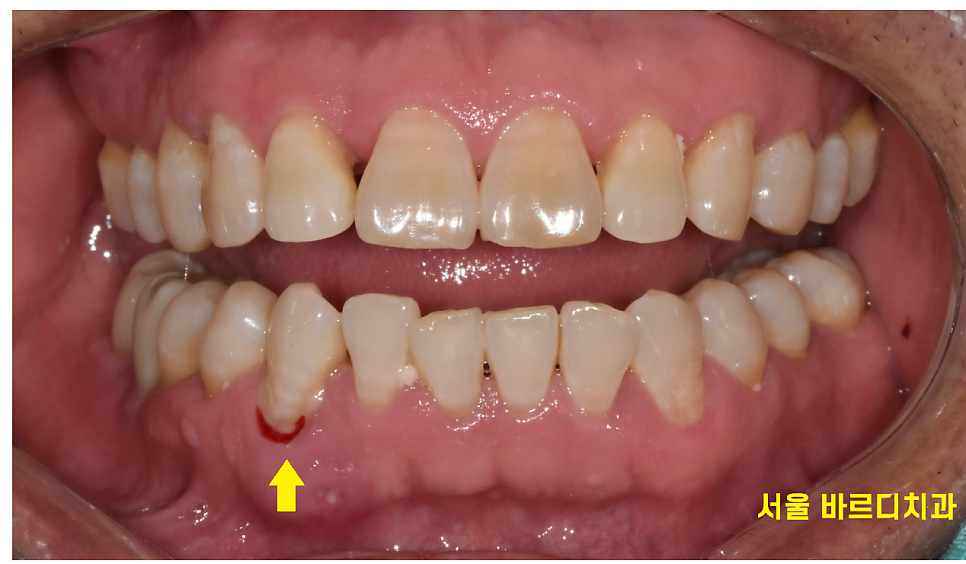

작은 자극에도 잇몸에서 피가 나기도 하고

위의 사진처럼 잇몸이 붓거나 피가나고

음식을 씹을 때 시리거나 아플 수 있습니다.

잇몸에서 노란색 또는 하얀색 고름같은 것도 나올 수 있고요